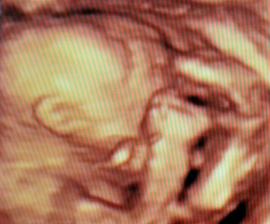

✿♥♥♥♥Bude to dievčatko!!!!! ♥♥♥♥✿

Bude to Stella 🙂

krasne 3D sono 🙂